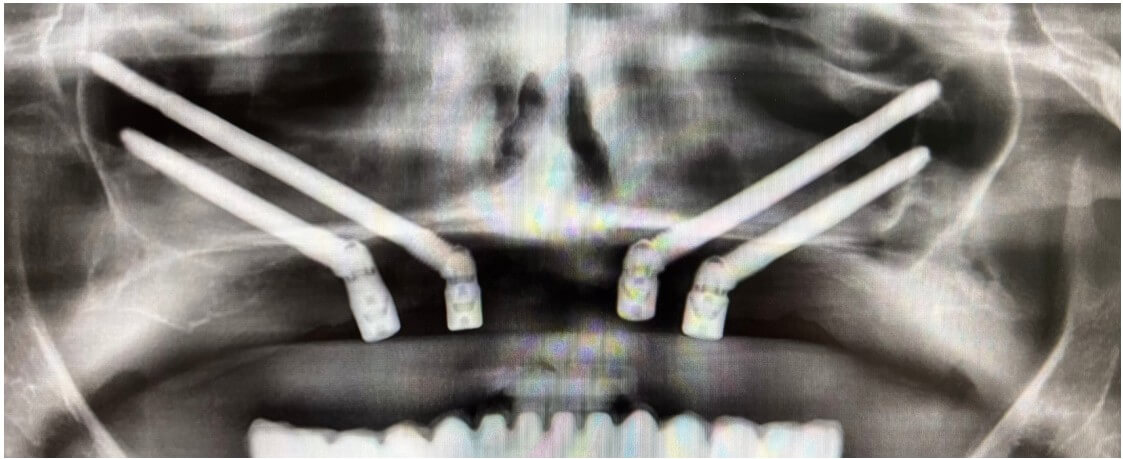

Colocamos los implantes cigomáticos según las guías quirúrgicas que hemos diseñado en planificación 3D.

Podemos hacer carga inmediata. Todo se realiza bajo sedación intravenosa monitorizada

Se colocan 4 implantes Zygoma según planificación 3D guiada bajo sedación IV, Carga inmediata a las 24 horas.